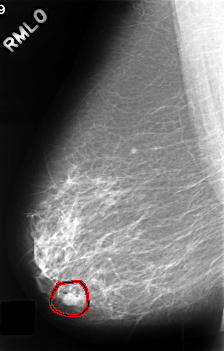

ics_version 1.0 filename C-0390-1 DATE_OF_STUDY 16 5 1996 PATIENT_AGE 66 FILM FILM_TYPE REGULAR DENSITY 2 DATE_DIGITIZED 9 11 1998 DIGITIZER LUMISYS LASER SEQUENCE LEFT_CC LINES 4424 PIXELS_PER_LINE 2928 BITS_PER_PIXEL 12 RESOLUTION 50 OVERLAY LEFT_MLO LINES 4472 PIXELS_PER_LINE 2952 BITS_PER_PIXEL 12 RESOLUTION 50 OVERLAY RIGHT_CC LINES 4520 PIXELS_PER_LINE 2960 BITS_PER_PIXEL 12 RESOLUTION 50 OVERLAY RIGHT_MLO LINES 4560 PIXELS_PER_LINE 2904 BITS_PER_PIXEL 12 RESOLUTION 50 OVERLAY |

FILE: C_0390_1.RIGHT_MLO.OVERLAY TOTAL_ABNORMALITIES 1 ABNORMALITY 1 LESION_TYPE MASS SHAPE LOBULATED MARGINS CIRCUMSCRIBED ASSESSMENT 4 SUBTLETY 5 PATHOLOGY BENIGN TOTAL_OUTLINES 1 BOUNDARY |